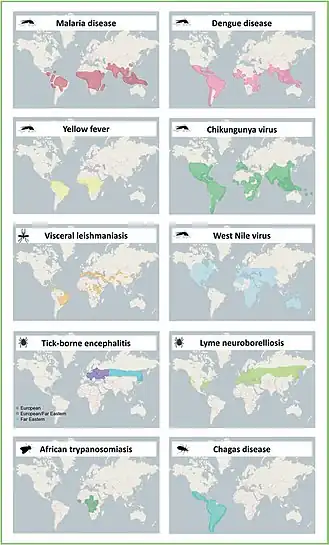

As vectors of disease

In addition to stings and bites causing discomfort in of themselves, bites can also spread secondary infections if the arthropod is carrying a virus, bacteria, or parasite.[8] The World Health Organization (WHO) estimates that 17% of all infectious diseases worldwide were transmitted by arthropod vectors, resulting in over 700,000 deaths annually.[9] The table below lists common arthropod vectors and their associated diseases. The figure below represents endemic areas of common vector-borne diseases.